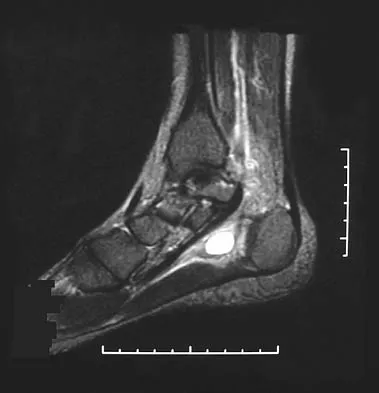

Question 14

A 30-year-old man has had intermittent swelling of his right ankle for the past 6 months. He denies any history of trauma. Radiographs reveal osteolytic changes on both sides of the joint. An axial CT scan and a T2-weighted MRI scan are shown in Figures 40a and 40b. He undergoes surgical excision. An intraoperative photograph and a biopsy specimen are shown in Figures 40c and 40d. What is the most likely diagnosis?

Explanation